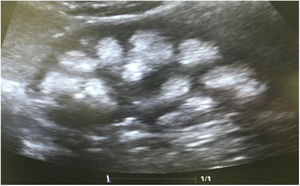

Casos clínicosCaso 1Paciente femenino de 4 años y 3 meses de edad. Peso al nacer 2.800g, talla 48cm y Apgar 8/9. Como antecedente presenta avidez por el agua y la sal. Poliuria y nicturia en la etapa de lactante. Fue hospitalizada en 11 ocasiones por fiebre sin foco aparente. A los 20 meses de edad fue diagnosticada de herpes zóster y tratada con aciclovir durante 7 días; a continuación, presentó un cuadro diarreico, deshidratación moderada y flacidez generalizada con incapacidad para caminar. Fue hospitalizada en el Hospital General de Zona con la sospecha de síndrome de Guillain-Barré; su peso era 9,5kg y la talla 82cm (ambos en percentil 10). Se observó hipopotasemia (2,5mEq/l) y acidosis metabólica. Tras instaurarse tratamiento intravenoso y la corrección del desequilibrio hidroelectrolítico, mejoró la fuerza muscular logrando la deambulación. Sin embargo, persistía la acidosis metabólica hiperclorémica. Los datos bioquímicos y los hallazgos de la ecografía aparecen en la tabla 2 y la figura 2, respectivamente. La valoración audiológica no mostró datos de hipoacusia neurosensorial. El estudio oftalmológico fue normal. Se realizó una prueba de acidificación urinaria con bicarbonato de sodio y acetazolamida según un protocolo descrito previamente (prueba de pCO2 urinaria máxima)11–13. La prueba se realizó sin complicaciones, fue bien tolerada y se consideró valida al conseguirse una bicarbonaturia superior a 80mEq/l. Se cuantificó una pCO2 urinaria máxima de 80mmHg a los 60min (anormal<70mmHg) (tabla 3). Se comprobó que la paciente es portadora de la misma mutación que su madre. Después de 3 años de tratamiento con álcalis ha mejorado el peso y la talla, a saber, 16,5kg (percentil 47) y 103cm (percentil 34), respectivamente. En la actualidad recibe tratamiento con citrato de potasio (4,5mEq/kg/día) con lo que ha remitido la hipercalciuria. La TA es normal (89/59mmHg).

Paciente masculino de 8 años y 11 meses de edad sin antecedentes perinatales de importancia (peso 2,9kg, talla 50cm y Apgar 9/10). Avidez por el agua y la sal desde los 2 años de edad, aproximadamente. Precisó 3 hospitalizaciones durante su primer año de vida por episodios de deshidratación moderada. Acudió hasta en 24 ocasiones al servicio de urgencias de su localidad por la presencia de fiebre. En algunas ocasiones se catalogó de infección de vías respiratorias, si bien, en la mayoría de los casos no se detectó una causa aparente de la misma. Al efectuarse el diagnóstico de ATRd a su hermana, se realizó el abordaje diagnóstico. Su peso era 18kg (percentil 5) y la talla 111cm (percentil 3). Se observó acidosis metabólica hiperclorémica con anión restante normal, hipercalciuria, hipocitraturia severa (tabla 2) y nefrocalcinosis grado III. La valoración audiológica fue normal. La pCO2 urinaria máxima también fue normal (tabla 3). También, después de tres años de tratamiento con álcalis han mejorado tanto el peso (23kg, percentil 8) como la talla (122cm, percentil 17). Recibe tratamiento con citrato de potasio (5mEq/kg/día). El estudio genético mostró la misma mutación que su madre y su hermana.